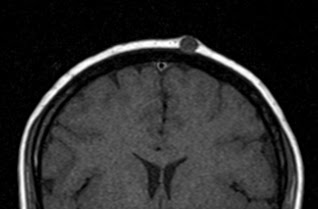

Клинически пиломатриксома представляет собой узел шаровидной или шальной формы, хорошо пальпируемый под поверхностью кожи. Характерная особенность этой опухоли - ее плотная консистенция. Опухоль не спаяна с окружающими тканями, подвижна, иногда умеренно болезненна при пальпации. Обычный размер новообразования 0,5-3 см и более. В начале заболевания расположенный в глубоких слоях кожи опухолевый очаг больших размеров практически не заметен и не вызывает никаких субъективных ощущений у пациента. С течением времени, постепенно увеличиваясь в размepax, опухоль начинает выбухать над поверхностью кожи, которая иногда выглядит истонченной, атрофичной, гиперемированной, может шелушиться и порываться коркой (изредка встречаются пигментные формы). Больные начинают предъявлять жалобы на гуд, жжение, покалывание и (чаще всего при локализации на лице) на онемение.

Клинически злокачественная пиломатриксома представляет собой узел диаметром от 1 до 20 см (в среднем 4 см). Его консистенция в зависимости от степени кальцификации опухолевых тканей варьирует от мягкой до плотной. Опухоль обычно располагается на голове и шее (57%). Наиболее частые локализации, в порядке убывания: шея, околоушные и поза-диушные поверхности, волосистая часть головы. Изредка описывают злокачественные пиломатриксомы грудной клетки (13%), спины (11%), верхних (10%) и нижних (9%) конечностей. У детей опухоль также преимущественно (в 50% случаев) располагается на голове и шее, но ее диаметр меньше (в среднем 2 см), а максимальный размер не превышает 4см.